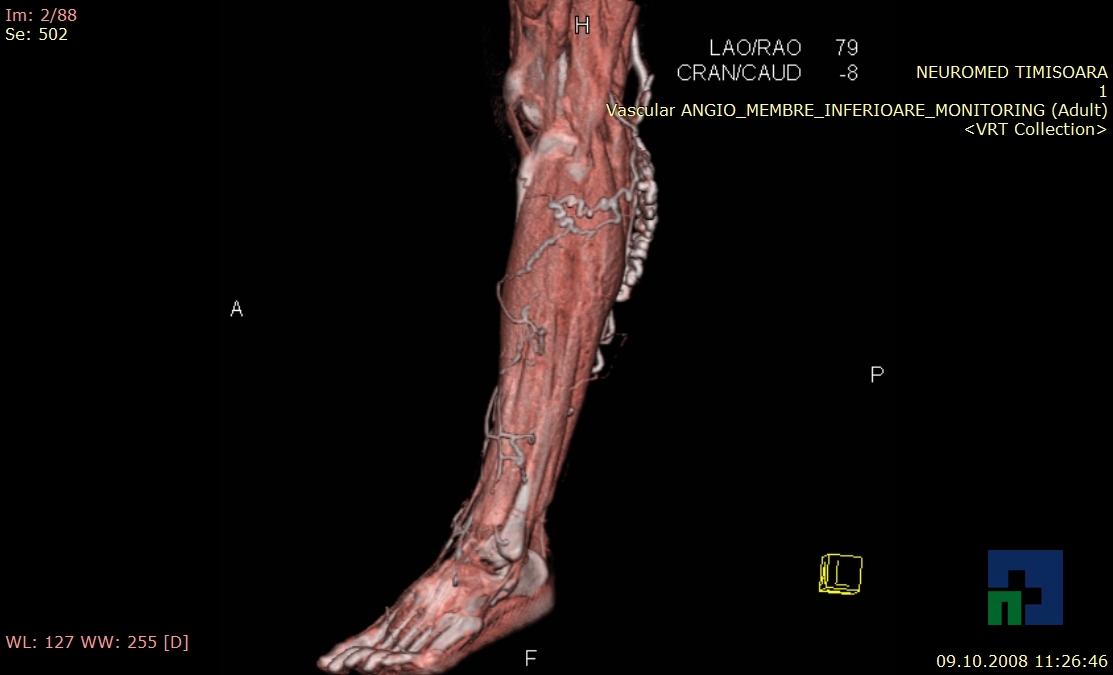

Examinare de rutină cerebrală, nativ și cu substanță de contrast (SDC) pentru diagnosticul:

- Accidentelor vasculare cerebrale ischemice sau hemoragice